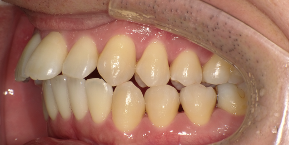

34歳女性のビフォーアフター

| 診断 | 叢生(デコボコがある状態)、開咬、下顎前突 |

| 治療方針 | インビザラインシステムにて主にIPR(歯と歯の間をわずかに削合してスペースを獲得する方法)を組み込んだ動的矯正治療を行った叢生改善と、開咬の改善のため臼歯部圧下をメインとした動的治療を行い、保定を行う。 |

| 治療費 ※ | 99万7千円(診断、型取り、PMTC、保定装置を含む料金) |

| 治療期間 | 3年5か月 |

| リスク | 1日20時間以上マウスピースを使用できない場合、歯が動かない可能性がある。装着時や食事時に痛みを伴う。歯肉退縮や虫歯になるおそれがある。また、指導通りに装着できていない場合や適切なブラッシングが出来ていないとそのリスクが高くなる。歯根が短くなることがある。ごくまれに歯の神経が損傷してしまうことがある。過去にぶつけたり深い虫歯治療をしたことがあるとそのリスクはやや高くなる。矯正後には保定装置が必要。適切な使用ができない場合、後戻りの原因となる。将来的に歯並びが動いて再矯正が必要な場合がある。舌癖が強い場合や正常に生えていない親知らずがある場合、その可能性が高くなる。 |

※ 治療費は、治療当時の費用で、現在の費用と異なる可能性があります。現在の費用は治療費のページでご確認くださいませ。